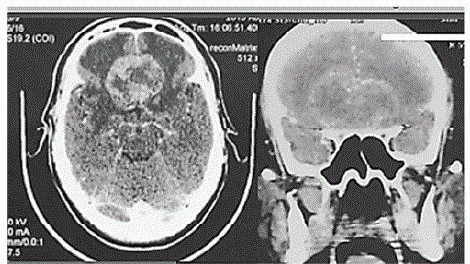

Considere um paciente de 59 anos de idade, com 90 kg, hipertenso e tabagista. Ele é levado ao hospital por familiares em razão de cefaleia persistente e progressiva. Os familiares relatam, ainda, alteração de comportamento há aproximadamente dois meses, associada à diminuição global de força. Ao exame, o paciente está pouco colaborativo, irritado, com fala inapropriada e hiposmia, sem deficits focais ao exame. Constatam-se AC = RC2T com BNF; FC = 82 bpm; AP = MVF sem RA; FR = 18 irpm; PA = 150 mmHg x 85 mmHg; e SatO2 = 97%. É realizada a tomografia computadorizada (TC) de crânio, conforme a imagem apresentada.

No estudo de RM, fase pré-contraste, a lesão provavelmente se apresentará isointensa em T1WI e hipointensa em T2WI.